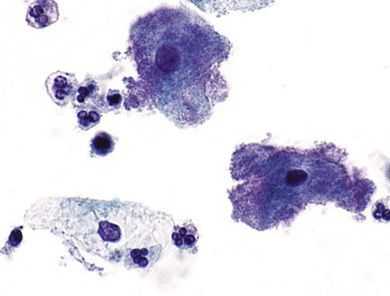

Для выявления уреаплазм используются только прямые методы выявления: бактериологический и молекулярно-генетический. Определение антител: IgG, IgA, IgM неинформативно. Материалом для исследования могут служить отделяемое мочеполовых органов, моча, вагинальный секрет и др.

- Бактериологическое исследование (бакпосев, культуральный метод) позволяет определить концентрацию микроорганизмов, но не различает виды Ureaplasma urealyticum и Ureaplasma parvum. В случае положительного результата будет обозначено: «Получен рост Ureaplasma urealyticum в концентрации 10 х КОЕ/мл», что может означать и U.urealyticum, и U.parvum.

- Молекулярно-генетическое исследование (полимеразная цепная реакция, ПЦР) определяет уреаплазмы с точностью до вида. При этом более современное количественное исследование в реальном времени (так называемая real-time PCR) определяет концентрацию микроорганизмов в формате «геном-эквивалент на миллилитр», это на один логарифм больше, чем традиционные КОЕ/мл [15] .

Прямая иммунофлюоресценция (ПИФ) и иммунофлюоресцентный анализ (ИФА) менее информативны при уреаплазмозе, чем молекулярно-генетические и бактериологические исследования. Их применяют только при отсутствии последних.

Не смотря на то, что сегодня клиническая венерология обладает широким перечнем современных диагностических методов, диагностика уреаплазмоза остается затруднительной из-за сложности обнаружения уреаплазм в ассоциации присутствующих микроорганизмов. По результатам микроскопии можно только предположить наличие уреаплазм (число лейкоцитов в мазке может быть несколько повышено или в норме). Для выявления уреаплазм венерологи применяют различные диагностические методики:

- Микроскопия для диагностики уреаплазмоза не применяется, поскольку микроорганизм имеет очень маленький размер и его не увидеть под микроскопом. К тому же эти организмы лишены клеточных стенок, поэтому на них невозможно выполнить окрашивание по Граму. Микроскопия проводится только для оценки состояния микрофлоры влагалища и степени лейкоцитоза.